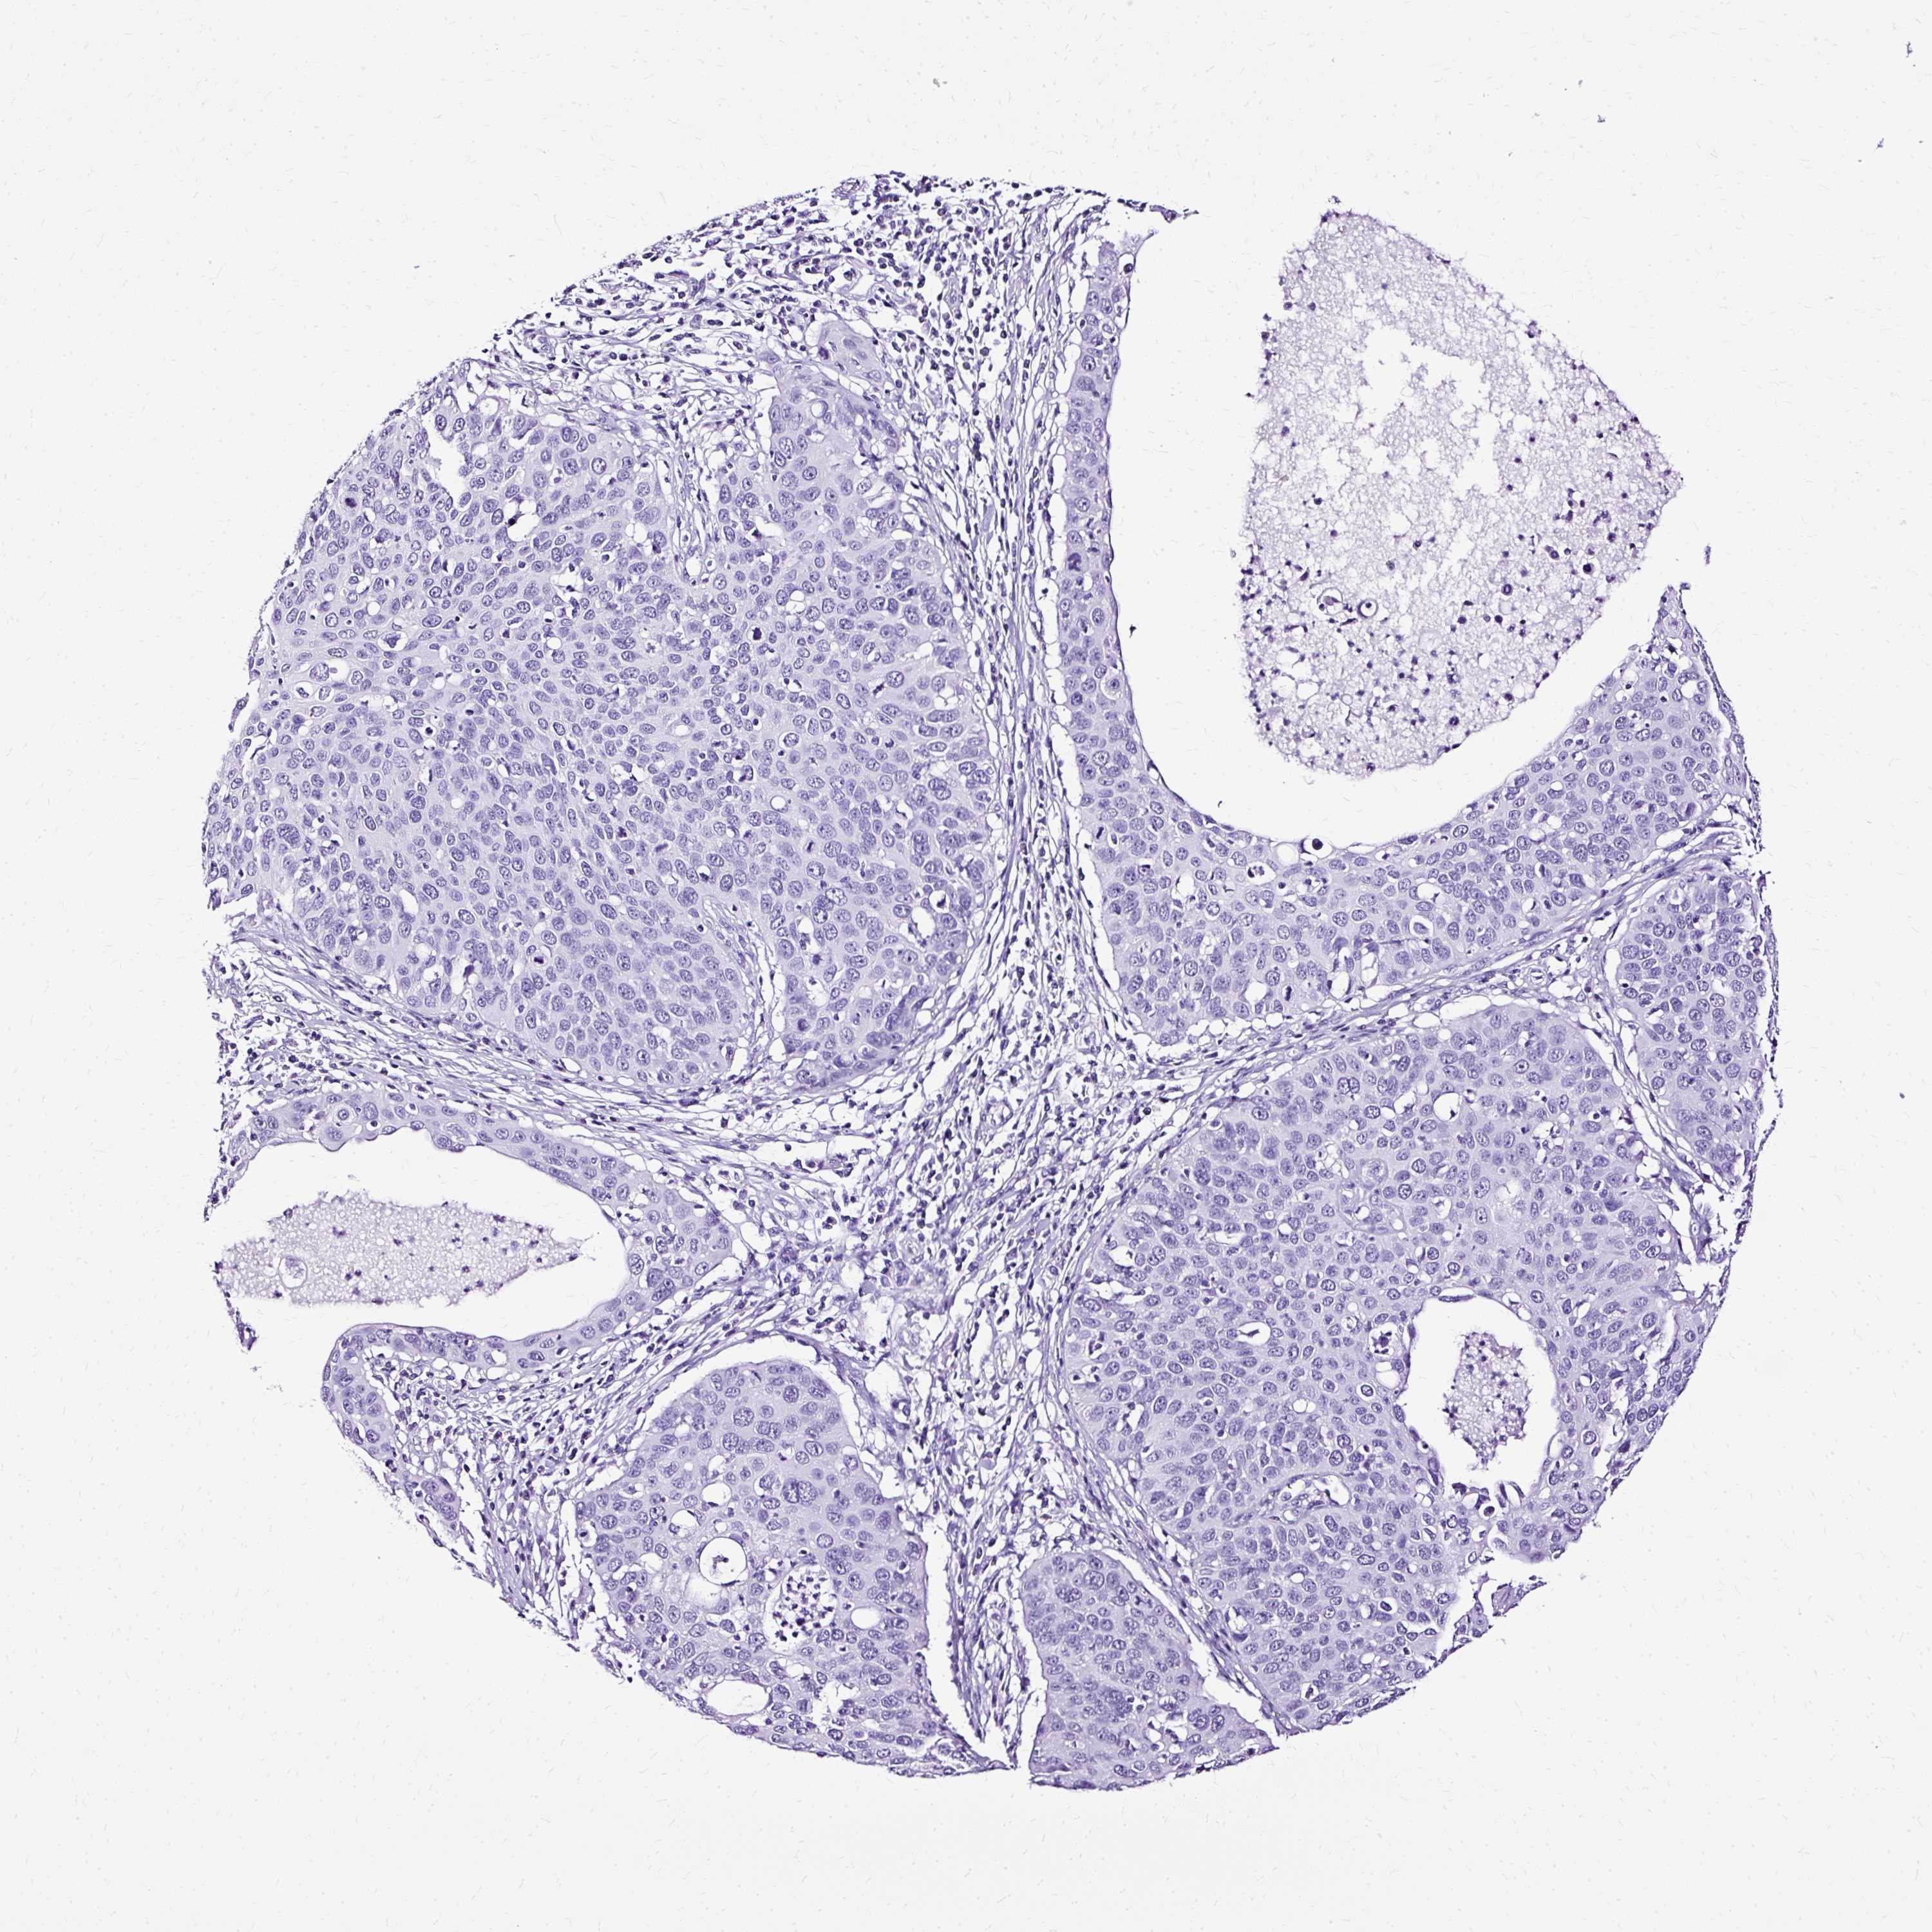

CERVICAL CANCER - Protein expressioni

A mouse-over function shows sample information and annotation data. Click on an image to view it in a full screen mode. Samples can be filtered based on level of antibody staining by selecting one or several of the following categories: high, medium, low and not detected. The assay and annotation is described here.

Note that samples used for immunohistochemistry by the Human Protein Atlas do not correspond to samples in the TCGA dataset.

Antibody stainingi

Antibody staining in the annotated cell types in the current human tissue is reported as not detected, low, medium, or high, based on conventional immunohistochemistry profiling in selected tissues. This score is based on the combination of the staining intensity and fraction of stained cells.

Each image is clickable and will lead to virtual microscopy that enables deeper exploration of all samples and also displays staining intensity scores, fraction scores and subcellular localization as well as patient and tissue information for each sample.

Antibody HPA050818

Antibody HPA054671

Staining

High

Medium

Low

Not detected

Intensity

Strong

Moderate

Weak

Negative

Quantity

>75%

75%-25%

<25%

None

Location

Nuclear

Cytoplasmic/membranous

Cytoplasmic/membranous,nuclear

Squamous cell carcinoma, NOS

Adenocarcinoma, NOS